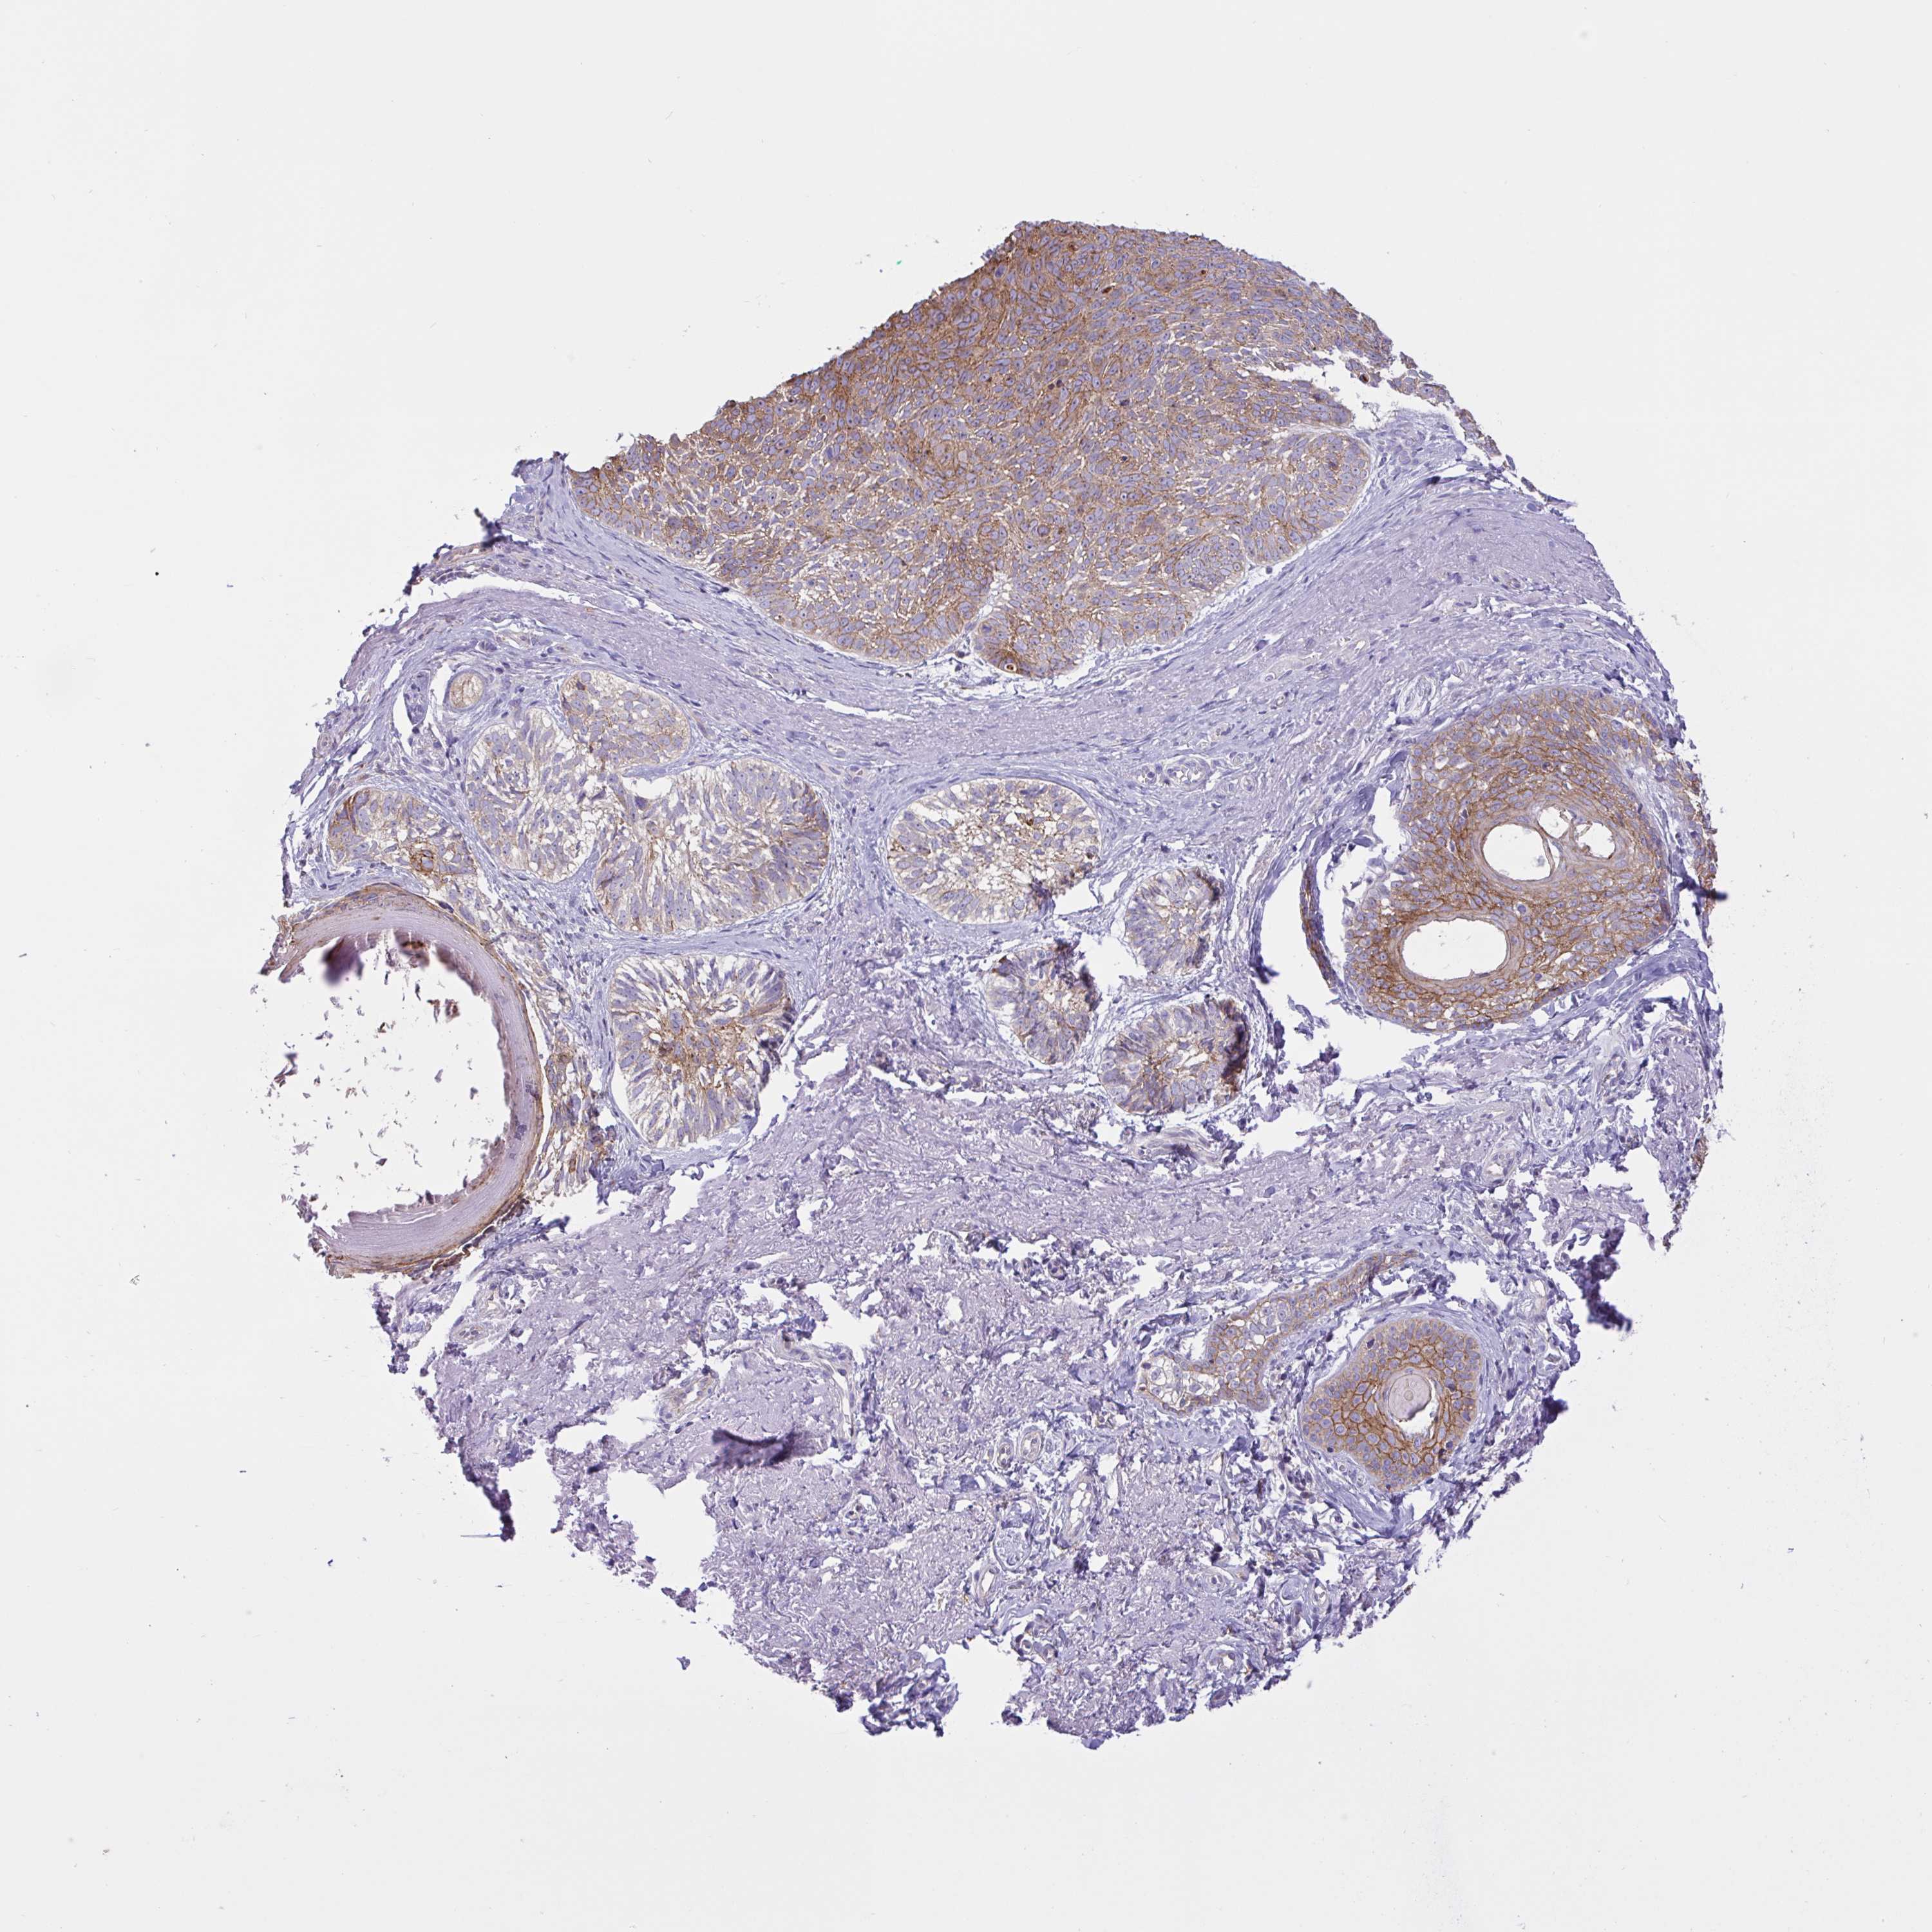

Basal cell and squamous cell cancer

SKIN CANCER - Protein expressioni

A mouse-over function shows sample information and annotation data. Click on an image to view it in a full screen mode. Samples can be filtered based on level of antibody staining by selecting one or several of the following categories: high, medium, low and not detected. The assay and annotation is described here.

Antibody stainingi

Antibody staining in the annotated cell types in the current human tissue is reported as not detected, low, medium, or high, based on conventional immunohistochemistry profiling in selected tissues. This score is based on the combination of the staining intensity and fraction of stained cells.

Each image is clickable and will lead to virtual microscopy that enables deeper exploration of all samples and also displays staining intensity scores, fraction scores and subcellular localization as well as patient and tissue information for each sample.

Antibody HPA049265

Antibody CAB037328

Staining

High

Medium

Low

Not detected

Intensity

Strong

Moderate

Weak

Negative

Quantity

>75%

75%-25%

<25%

None

Location

Nuclear

Cytoplasmic/membranous

Cytoplasmic/membranous,nuclear

Basal cell carcinoma